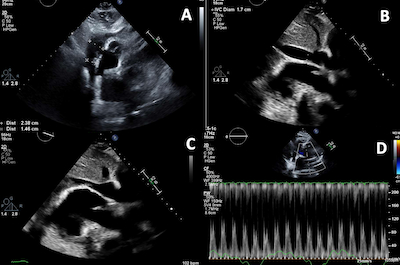

A 68-year-old woman, one month after bioprosthetic mitral valve replacement for severe mitral regurgitation, presented with fatigue and mild dyspnea on exertion. She was hypotensive and tachycardic, with pulsus paradoxus on exam. Transthoracic echocardiogram revealed a small anterior pericardial effusion and echocardiographic features consistent with tamponade physiology. A large right-sided pleural effusion was also discovered on CT imaging. She underwent urgent thoracentesis, after which tamponade findings resolved, and her symptoms markedly improved without pericardiocentesis.

This case highlights an uncommon but clinically significant cause of tamponade physiology: extracardiac compression from a large pleural effusion. While tamponade is usually due to pericardial fluid, elevated intrathoracic pressure from a pleural effusion can similarly impair diastolic filling and cause classic tamponade. The presence of a small pericardial effusion initially raised concern for being the primary etiology of tamponade, but resolution of symptoms and echocardiographic findings after thoracentesis clarified the source. This underscores the importance of considering alternative causes of tamponade physiology, particularly in postoperative cardiac patients with pleural effusion. Echocardiographic signs of tamponade are not specific to pericardial effusion; thus, clinical correlation and comprehensive imaging are essential to determine the true etiology. Timely recognition of pleural effusion-induced tamponade enables effective stabilization through a less invasive intervention and obviates unnecessary invasive cardiovascular procedures.